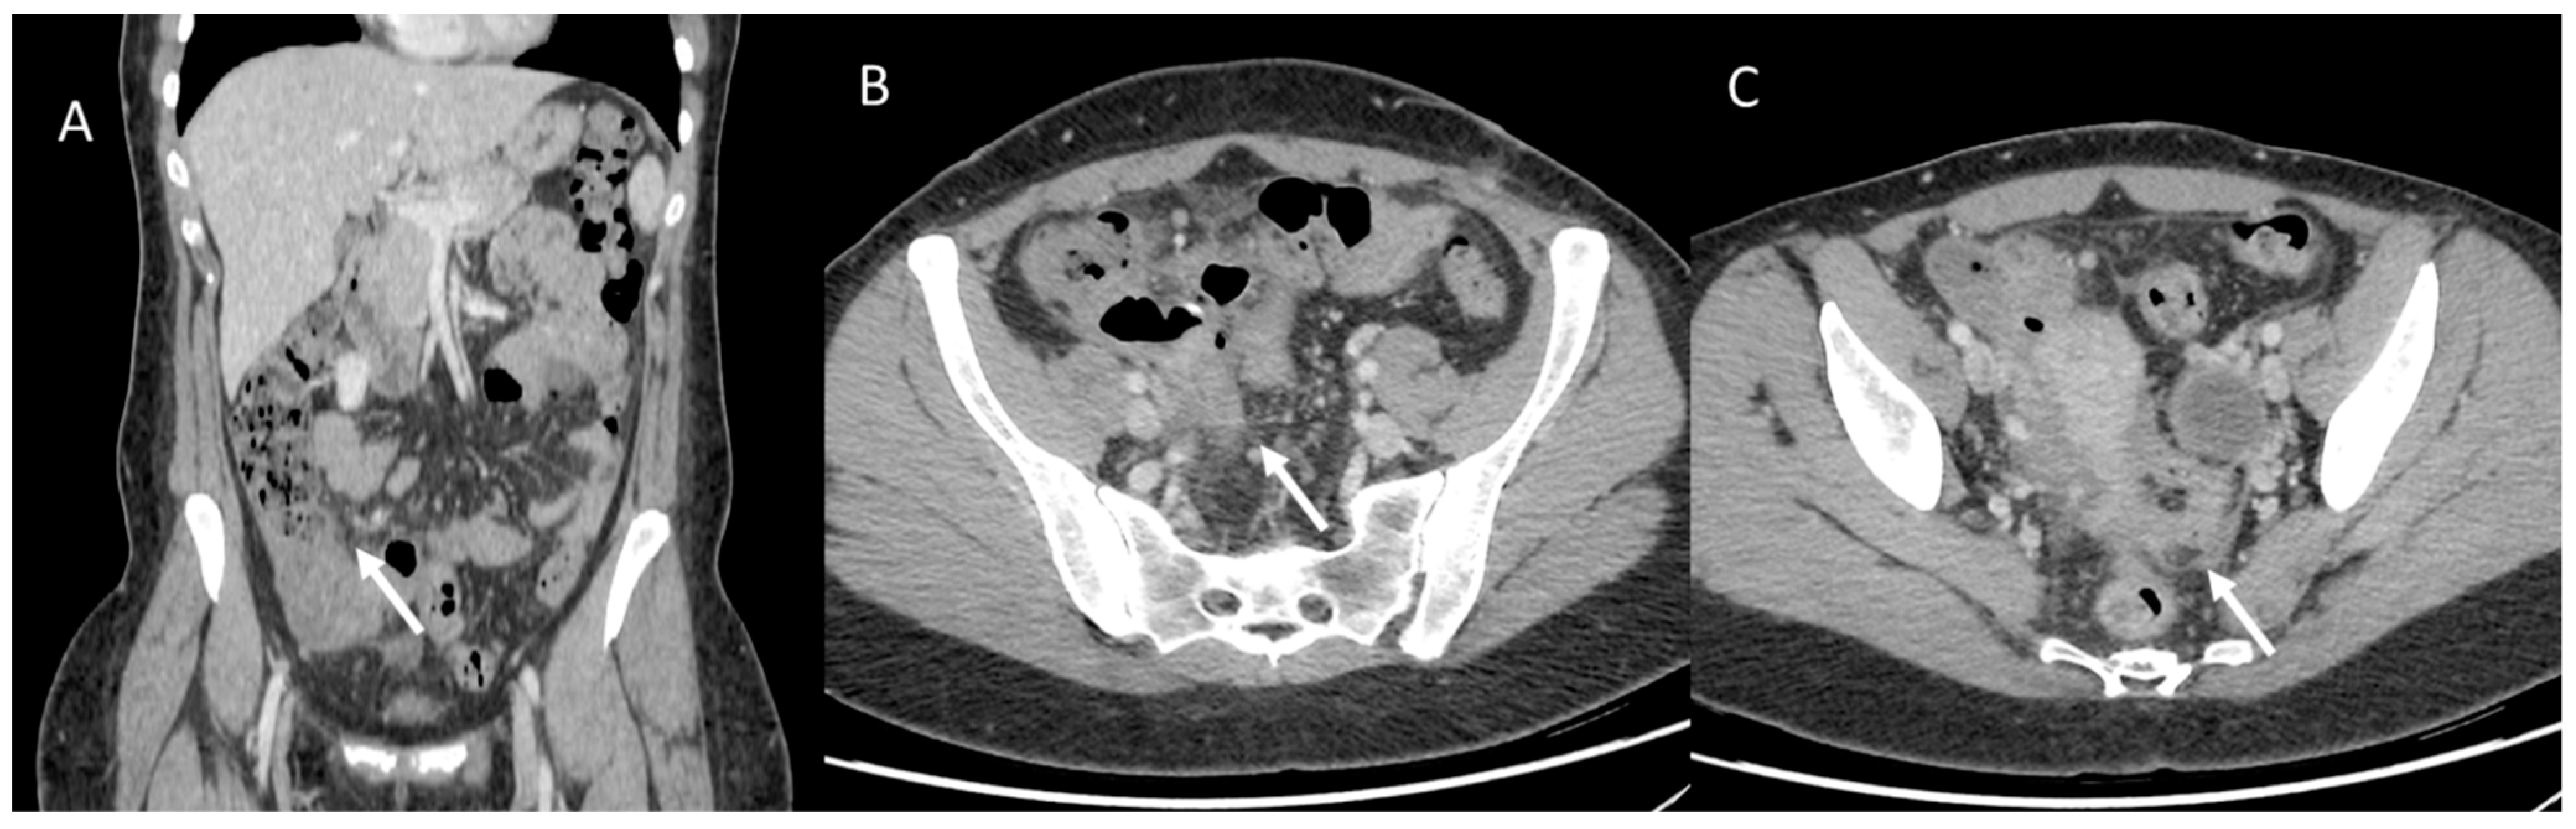

However, gender disparities are still a poorly considered aspect of CRC management. Women have a higher risk of developing right (proximal) colon cancer, which is associated with a more aggressive form of neoplasm than descending colon cancer, which is more typically male (Figure 6 and Figure 7) [137]. Underlying these gender differences are different genetic polymorphisms, epigenetic and hormonal factors, as well as a number of modifiable environmental factors, including lifestyle [138].

Figure 6.

Woman with operated appendiceal tumor ((A): in coronal plane, arrow). CT assessment of peritoneal carcinomatosis ((B,C), arrow).

Figure 7.

Man with transverse colon cancer (white arrows): in (A) (axial) and (B) (coronal) CT assessment.